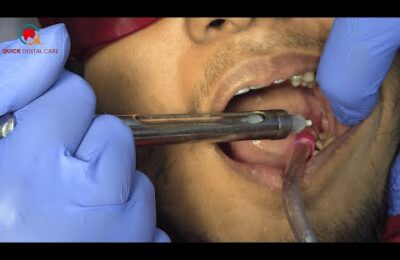

Root Canal Treatment Process | Everything You Need to Know! Part-1 #rootcanal #dentaltreatment

Welcome to our detailed guide on root canal treatment! In this video, we explain the full root canal procedure step